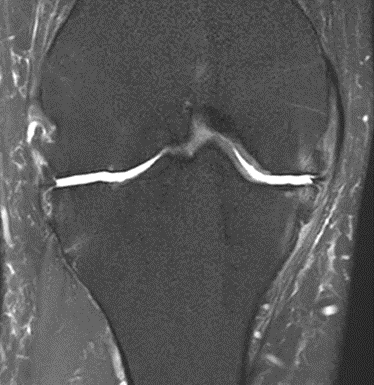

MRI scans illustrating the improvements regarding Group 2 are presented below, showing pre-treatment images with evident cartilage defects, pronounced bone marrow edema, and synovial inflammation, followed by post-treatment scans demonstrating improved joint structure, reduced edema, and decreased inflammation (Figures 12-29).

MRIs of Group 2

MRIs of Group 1

To provide a comparative perspective, additional MRI scans from Group 1 are shown subsequently. While patients in this group also displayed reductions in bone marrow edema, effusion, and synovitis, the improvements appeared less pronounced than those seen with the combined therapy. Pre-treatment MRI scans revealed extensive edema and synovial inflammation, which were partially reduced at the 2-month follow-up. However, residual joint effusion and subtle signs of inflammation remained present in some cases. These findings further support the potential benefit of combining the ChondroFiller® liquid with MSC therapy to achieve more comprehensive structural improvements and facilitate enhanced cartilage regeneration (Figures 30-41).